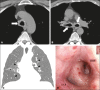

Primary tracheobronchial amyloidosis